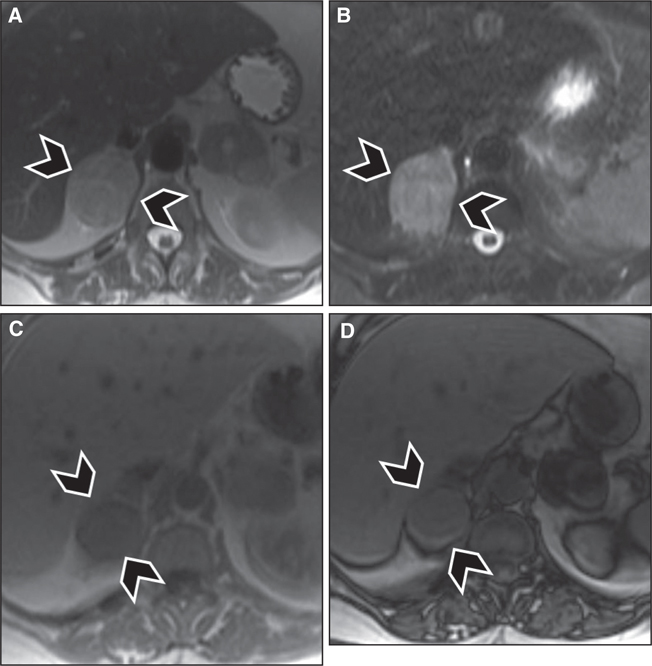

Fig 5

Figure 5 Right adrenal pheochromocytoma (arrowheads) in a 72-year-old female patient. Nonspecific signal intensity characteristics are seen, with intermediate to hyperintense signal seen on (A) T2-weighted images and (B) fat-suppressed T2-weighted images (turbo Inversion Recovery sequence), and hypointense signal seen on (C) in-phase T1-weighted images, and no signal loss on (D) out-of-phase images to suggest intralesional microscopic fat.